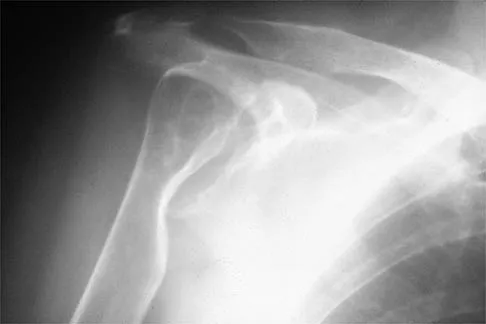

A 72-year-old woman who is right hand-dominant has severe pain in the right shoulder that has failed to respond to nonsurgical management. She reports night pain and significant disability. Examination reveals 30 degrees of active forward elevation. An AP radiograph is shown in Figure 27. Which of the following treatment options will provide the best functional improvement?

Figure 5 shows the radiograph of a 10-year-old girl who reports chronic shoulder pain after her gymnastics classes. Examination reveals pain on internal and external rotation but no instability. What is the most likely diagnosis?

A 79-year-old woman with polyarticular rheumatoid arthritis has had progressively increasing right shoulder pain for the past year, and nonsurgical management has failed to provide relief. Her neurologic examination is entirely normal, but she is unable to elevate her arm against gravity. An AP radiograph is shown in Figure 13. Treatment should consist of

A 42-year-old patient has had painful inferior subluxation of the glenohumeral joint following a recent cerebrovascular accident (CVA). Figure 34 shows the AP radiograph of the shoulder. Management should consist of

A 75-year-old woman has had severe shoulder pain for the past month. Her medical history includes hypertension and a total nephrectomy for renal cell carcinoma 7 years ago. Radiographs and sagittal MRI scans are shown in Figures 36a through 36d. A bone scan reveals this to be an isolated lesion. Biopsy findings are consistent with metastatic renal cell carcinoma. What is the most appropriate treatment for this patient?